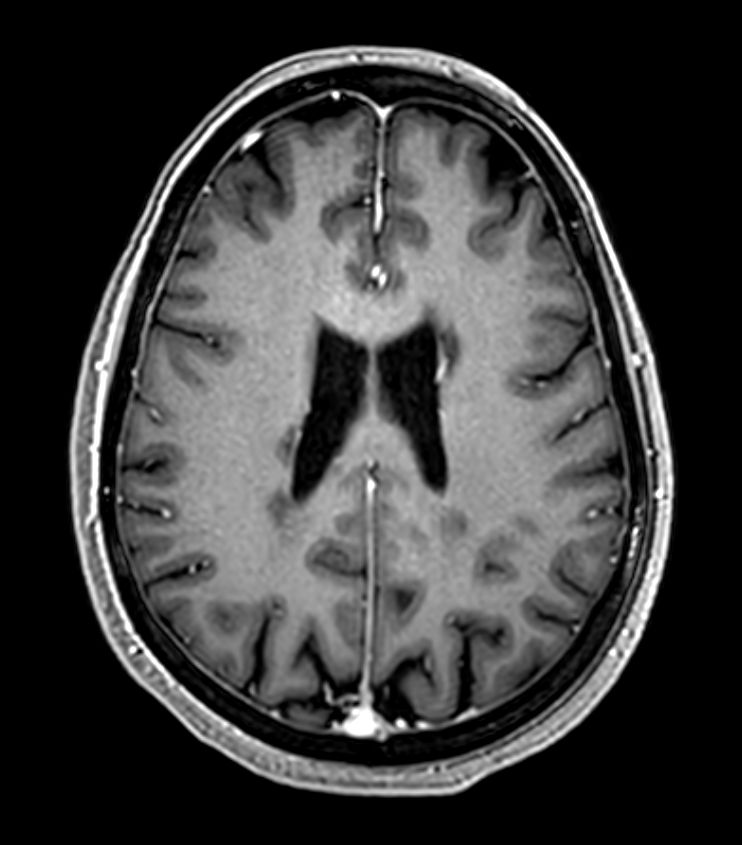

3D T1w FFE Compressed SENSE

3D T1w FFE (reformat) Compressed SENSE